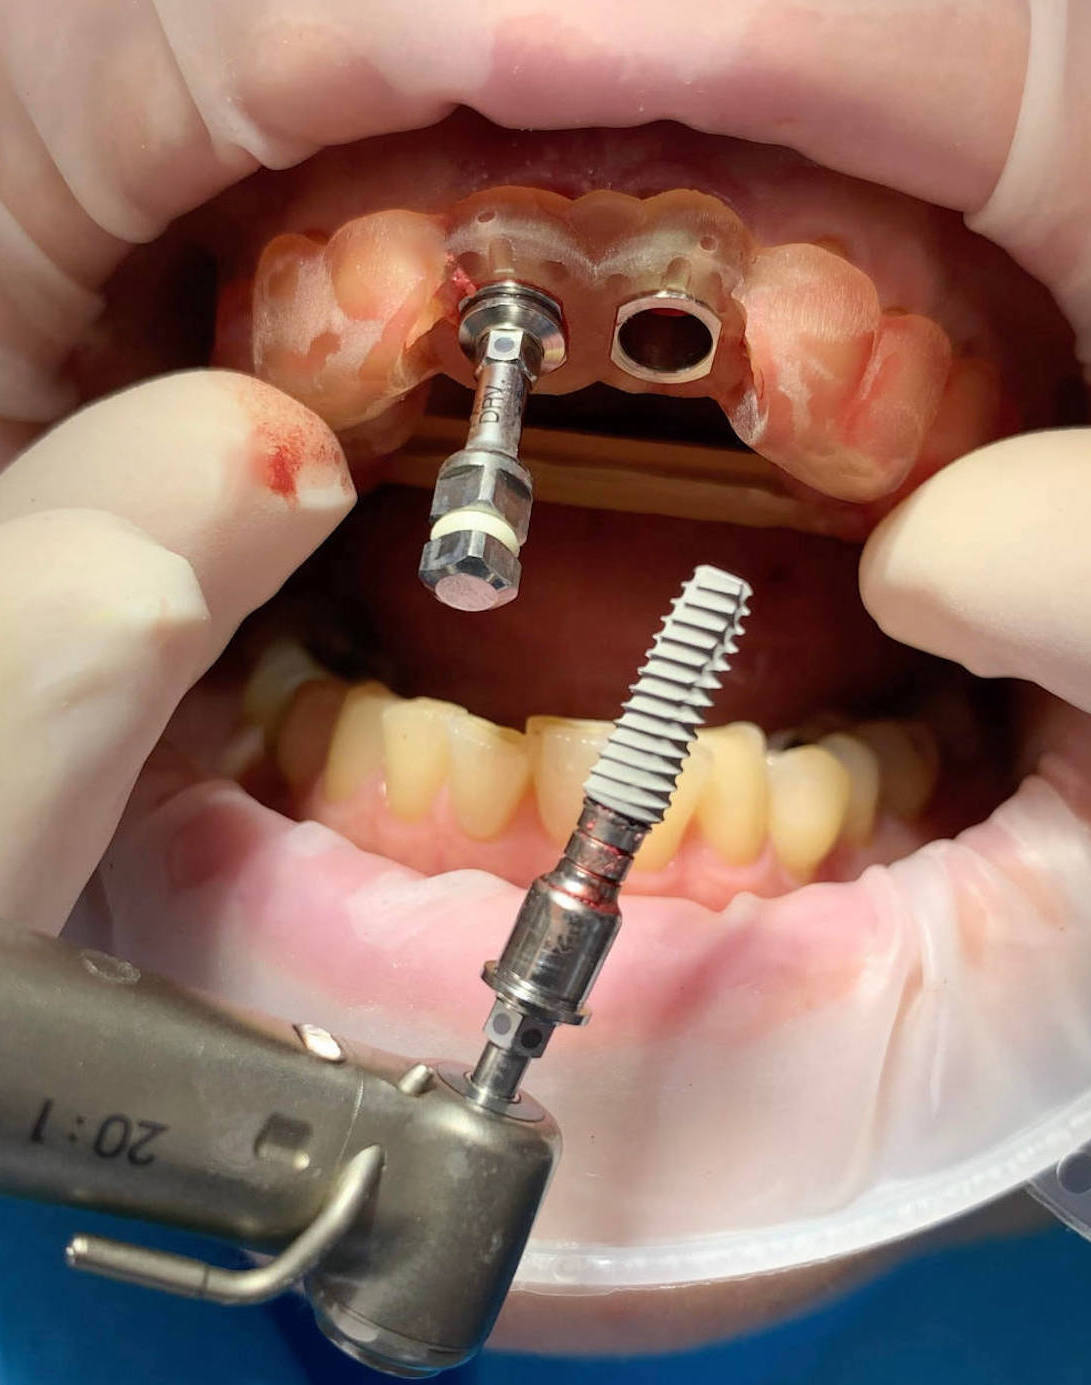

Jediným riešením bola extrakcia obidvoch zubov. Najväčšou obavou zo strany pacientky bola strata obidvoch predných zubov a následného fungovania bez nich pri práci s ľuďmi. Ideálnym riešením teda bola náhrada zubov implantátmi spolu s nasadením koruniek, a to počas jedného sedenia. V deň konzultácie bol pacientke urobený sken pomocou intraorálneho skeneru 3Shape TRIOS, ktorý nám umožňuje zobraziť 3D simuláciu ústnej dutiny. Pomocou softwaru 3Shape Implant Studio sme spojili dáta z intraorálneho skenu a CBCT, STL a DICOM súbory. V ďalšom kroku sme virtuálne vložili implantáty v správnej protetickej polohe, navrhli šablónu pre ich zavedenie, namodelovali individuálne abutmenty a korunky (obr. 4). Kompletné dáta sme exportovali pre frézovanie a 3D tlač. V laboratóriu sa pomocou 3D tlačiarne vytlačila chirurgická šablóna, ktorá nám slúži na presné zavedenie implantátov – použili sme implantačný systém Dentium Super Line. Následne boli vyfrézované zirkonové abutmenty a plastové dočasné korunky(obr. 5).

Následne sme použili protokol vŕtania a zavedenia implantátov cez šablónu (obr. 7, 8), na ktorej sme mali orientačné body pre správne napolohovanie implantátov, abutmentov a koruniek (obr. 9–14).